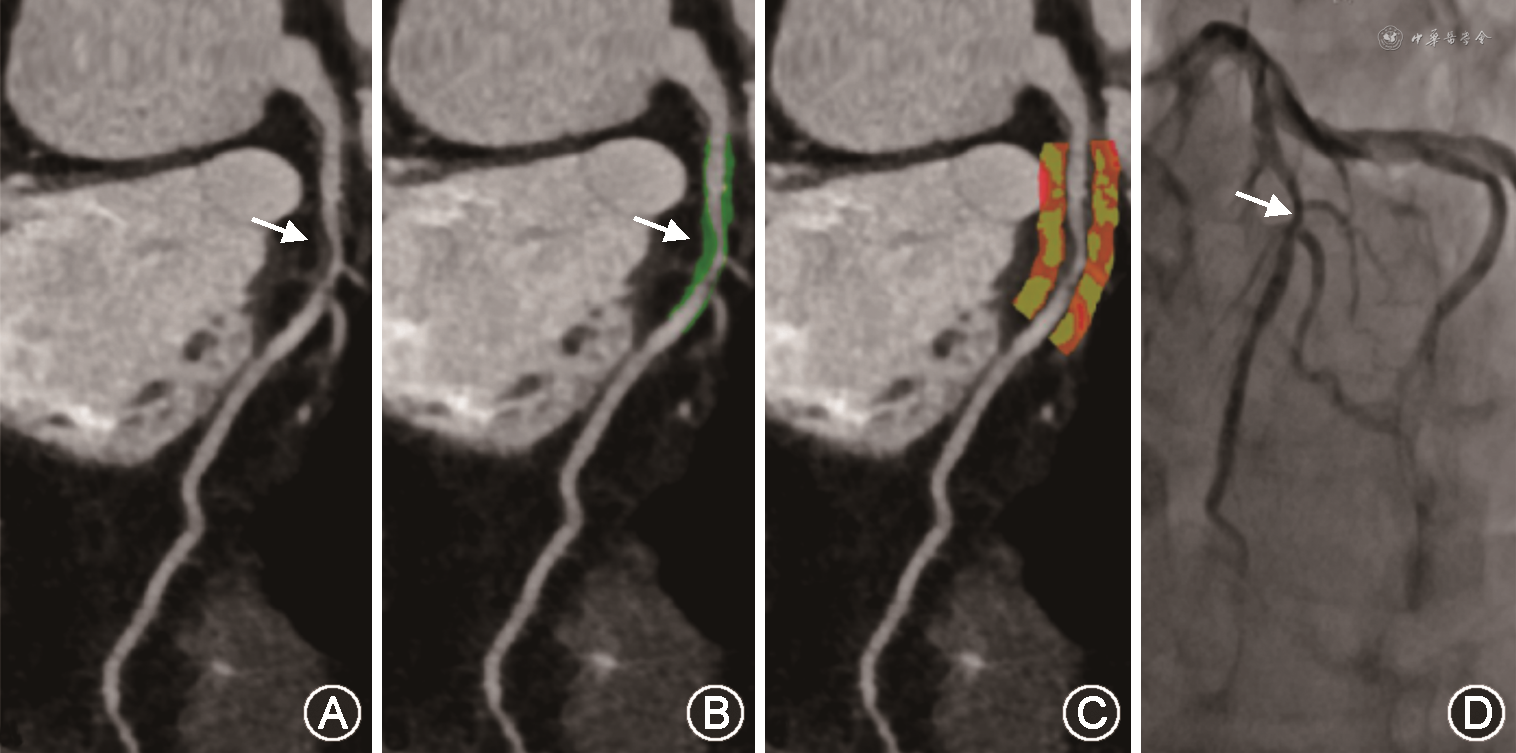

1. 斑块数据分析:将所有CCTA的数据传输至后处理工作站SyngoVia(德国西门子医疗),选择图像质量最佳的期相进行分析。使用专门的斑块分析软件Coronary Plaque Analysis 5.0(德国西门子医疗)在曲面重组图像上进行斑块定位和分析。首先,将CCTA图像导入斑块后处理软件后,自动提取冠状动脉树的中心线,操作者可对中心线进行手动调整,手动定位斑块的近端和远端,软件自动勾画出斑块,操作者可适度编辑,自动计算如下斑块指标:最小管腔面积(MLA)、狭窄程度、斑块长度、总斑块体积(TPV)(图1A、1B)。根据冠状动脉疾病报告与数据系统(CAD-RADS),将CCTA狭窄程度分为0、>0~25%、≥25%~50%、≥50%~70%、≥70%~100%、100%共6个等级[7]。

2. 斑块周围FAI分析:通过斑块分析软件Coronary Plaque Analysis 5.0(德国西门子医疗)进行斑块周围FAI的测量。以斑块起始处至斑块远端为纵向测量距离,以血管外壁直径为径向距离,从血管外壁向外圈定周围组织作为测量的范围。调整纳入计算的组织密度范围为-190~-30 HU,随后软件自动计算出斑块血管周围的脂肪密度的平均值(图1C)[10]。所有测量由一名有经验的放射科医师进行。为了检验测量结果的一致性,在完成第一次测量2个月后,随机抽取20例患者进行第二次测量,由两名有经验的放射科医师进行。将同一名医师前后测量的结果进行读者内一致性检验,将两名医师测量的结果进行读者间一致性检验。

通过冠状动脉或静脉注射腺苷(140~180 mg·kg-1·min-1)(中国石药银湖制药有限公司)使冠状动脉最大程度充血,然后使用6-或7-F引导导管,将FFR压力导丝放置在血管段狭窄远端至少20 mm处进行FFR测量,得到有创FFR的结果(图1D)。根据《冠状动脉血流储备分数临床应用专家共识》[11],FFR<0.75的病变宜行血运重建;FFR>0.80的病变为药物治疗的指征;FFR值在0.75~0.80为灰区,术者可综合患者的临床情况及血管供血的重要性,决定是否进行血运重建。根据一些大型临床研究,如《FFR指导低危稳定型心绞痛患者延迟PCI治疗的研究(DEFER研究)》以FFR<0.75作为心肌缺血的阈值[12]。本研究将FFR<0.75定义心肌特异性缺血。